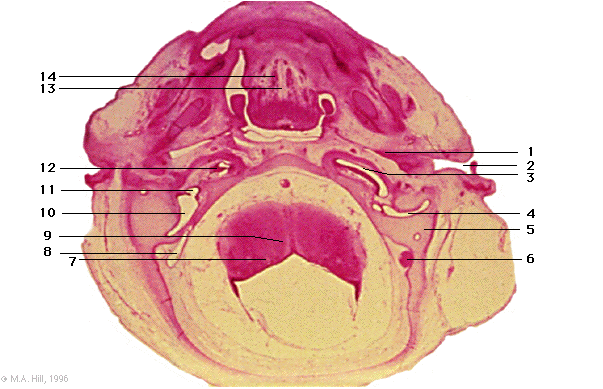

1 |

pharyngo-tympanic tube |

2 |

external acoustic meatus |

3 |

basal turn of cochlea duct |

4 |

lateral semicircular canal |

5 |

periotic capsule |

6 |

sigmoid sinus |

7 |

solitary tract |

8 |

endolymphatic sac |

9 |

myelencephalon (medulla) |

10 |

utricle |

11 |

saccule |

12 |

vestibular and spiral ganglion (VIII) |

13 |

floor of buccal cavity |

14 |

tongue musculature |